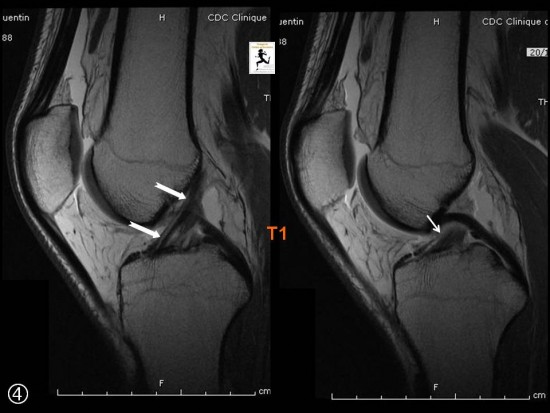

Tako so se pričele znova pojavljati težje po primarni reparaciji ligamenta. Trditev, da se sprednja križna vez ne zaraste je bila hitro ovržena, saj smo pri artroskopijah kolena po poškodbi sprednjega križnega ligamenta običajno ugotavljali, da se je le-ta zarastel, vendar običajno na napačno mesto – na zadnjo križno vez. To je bilo pravzaprav pričakovati, saj se glede na anatomijo in mehaniko poškodbe križni ligament strga običajno v zgornji tretjini oziroma izpuli iz femoralnega narastišča, ostalo pa potem opravi gravitacija. Zaradi gravitacije vez pade navzdol in se nato zabrazgotini na zadnjo križno vez.

Vsekakor pa je potrebno opraviti reparacijo vezi pravočasno. Študije so dokazale, da je ta časovni okvir tri tedne. V tem času je potrebno bolnike zajeti, jih klinično pregledati, opraviti magnetno resonančno preiskavo in nato tudi operirati, kar je pri nas in v obstoječem zdravstvenem sistemu zelo zahtevno.

Tehnika so poimenovali Ligamys. Gre za operacijo, pri kateri krn sprednjega križnega ligamenta ujamemo z do petimi šivi, s katerimi ga adaptiramo na femoralno narastišče. Nato to fiksacijo zavarujemo z notranjo oporo. Operacija poteka podobno kot klasična rekonstrukcija – artroskopsko, prav tako naredimo rez v predelu medialnega kondila tibije, skozi katerega vstavimo implantant. Njena velika prednost je, da v koleno ne vstopimo s svedrom, pač pa le z iglo, tako je posledično manj otekanja.

Slabost tehnike je, da z njo ne moremo rekonstruirati vseh križnih vezi, pač pa le tiste, kjer gre za rupturo v zgornji tretjini in pri kateri preostanek vezi ni preveč razcefran, da ga je še mogoče ujeti s šivi. Operacijo moramo opraviti v treh tednih od poškodbe.